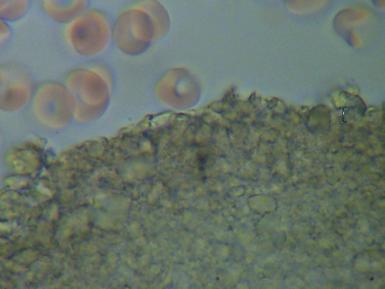

2.PASOŻYTY I GRZYBY

w zakwaszonym środowisku rozwijają się różnego rodzaju organizmy pasożytujące : robaki, grzyby, bakterie, wirusy i inne. Walka z nimi jest możliwa tylko przez zmianę środowiska z kwaśnego na zasadowe, w tym środowisku nie mogą się one rozmnażać i żyć.

We krwi widoczne są larwy i jaja pasożytów.

Komórki grzybów. W zależności od tego w jakim stopniu organizm zaatakowany jest przez grzyba widoczny jest obraz pojedynczych komórek lub całych kolonii i wtedy możemy mówić o bardzo niebezpiecznej dla organizmu grzybicy.